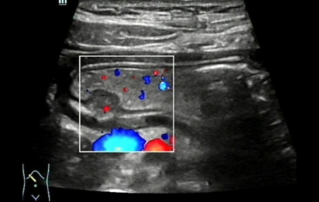

??? ?? ??? ?? ???? ? ??? ?? ??? ?? ??? ??? ??? ???. ???? ??? UWN+ ?? ?? ??? ?? MI??? ??? ??? ?? ?? ??? ?? ?? ?? ???, ?? ?? ?? ???? ??? ? ????.